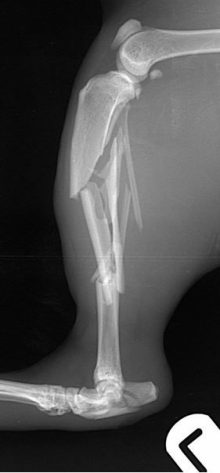

Bilateral PAX locking plate fixation in cat

Treatment of a highly comminuted humeral condylar fracture in a cat using bilateral PAX locking plate fixation A cat ...